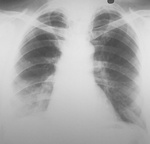

Снимков при поступлении у меня нет - есть описание: В легких умеренная перегрузка по МКК. Правый синус плохо просматривается ( жидкость ? ). Сердце умеренно расширено влево. Аорта плотная. Эти снимки в динамике, через 10 дней. А/б пациент не получал...

Это снимки от 28.06.12 года - прямой и правый боковой ( динамика )!

Изменения в верхушках есть, но не думаю, что ТБЦ. Для такого возраста характерно и в норме. Справа внизу похоже на инфильтрацию, но это возможна и ТЭЛА.

Справа, в нижнем легочном поле снижение прозрачности, возможно с верхушками и не связанное. Туб пробы делали?

Инфильтрация в в 9 и 10 справа с плевральной реакциией. А природа любая, но активный ТБС маловероятен. Если заказана КТ - нужно делать...

Обработанные снимки.

Снимки сделаны недопустимо «мягкими лучами», контраст чрезмерный и потому потеряно много информации в тенях и в светах. Всё, что упомянули коллеги, здесь может быть. Tbc, если и есть не может объяснить имеющуюся симптоматику. Скорей всего есть немного плеврального транссудата справа. Проверить на УЗИ – минутное дело.